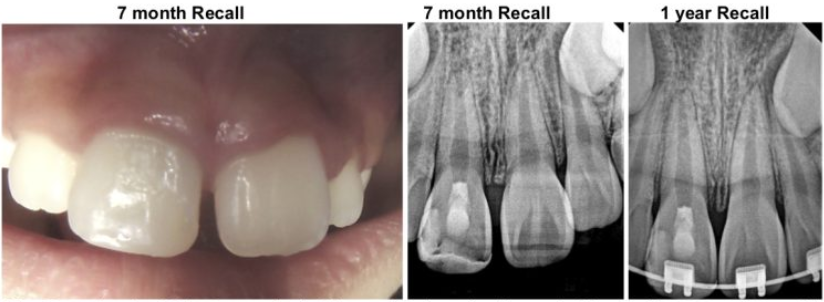

Treatment: Regenerative endodontic procedure was completed on the tooth #8. The preoperative abscess resolved completely. The tooth was restored with MTA and composite resin.

After 7 months, the PA lesion resolved with complete bone healing and with a positive response to cold test (endo ice). Orthodontic treatment was initiated to correct the occlusion and spacing with her orthodontist. Tooth #8 remained vital and continued to develop with the elongation of the root and the closure of the apical foramen/root end.